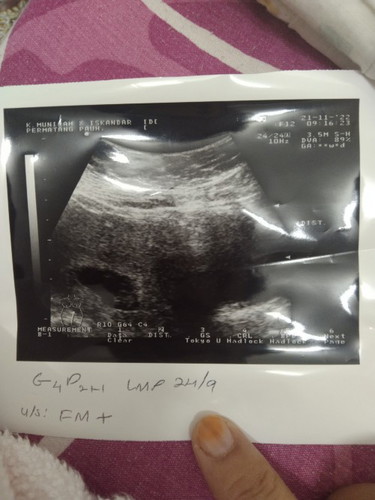

Alhamdulillah ikut tracker ni dh 8w.tadi pi scan tanya doc dah berapa minggu,doc cakap xbole nk ukur tepat sbb dia kata bdn sy berisi🤦nak tanya sister² 8w bby dah gerak² ke?sbb masa scan mmg sy nampak siap doc tunjuk dia dok gerak²#seriusnanya #ingintahu

Mama of 2 adventurous boy